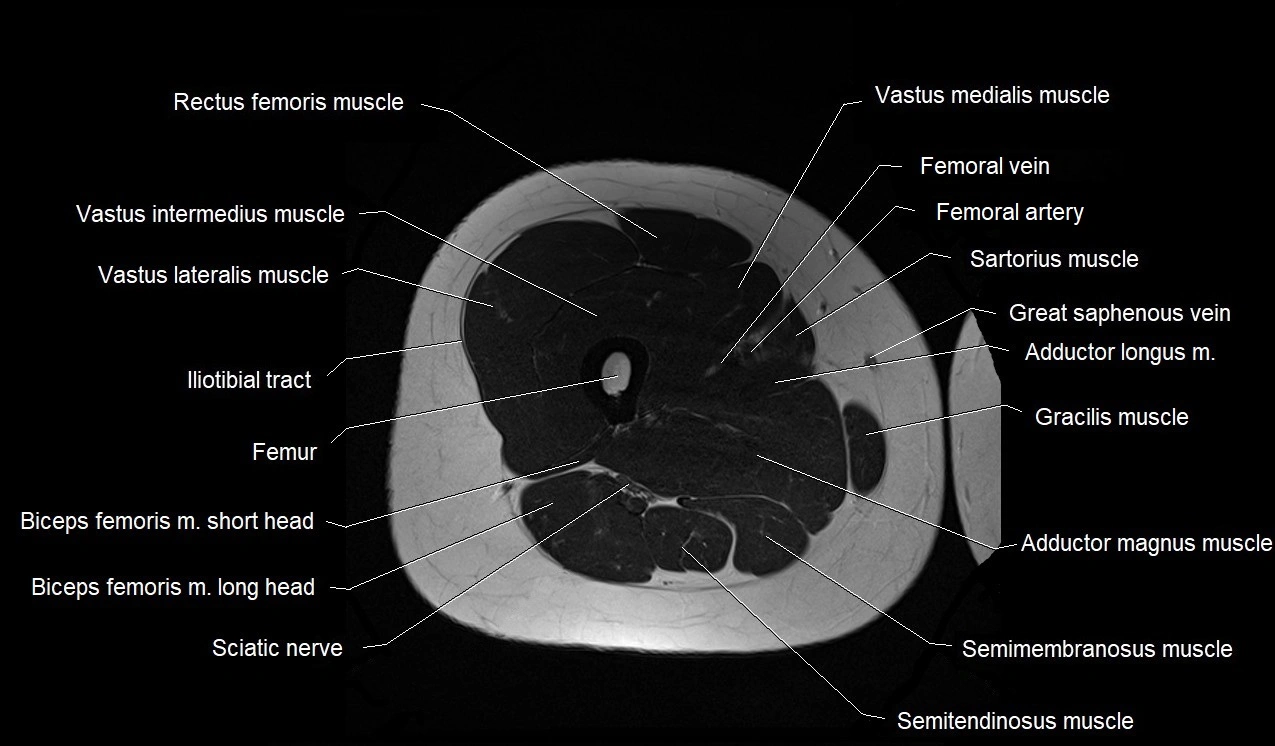

- Biceps femoris muscle (Long head)

- Biceps femoris muscle (Short head)

- Femoral artery

- Femoral vein

- Femur

- Gracilis muscle

- Iliotibial tract

- Rectus femoris muscle

- Sartorius muscle

- Semimembranosus muscle

- Semitendinosus muscle

- Tibial nerve

- Vastus intermedius muscle

- Vastus lateralis muscle

- Vastus medialis muscle